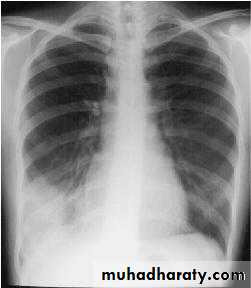

5-Lobar pneumonia and pleurisy, especially at the right base

Abdominal tenderness is minimal,

pyrexia is marked

+ve pleural friction rub or altered breath sounds on auscultation.

A chest radiograph is diagnostic.